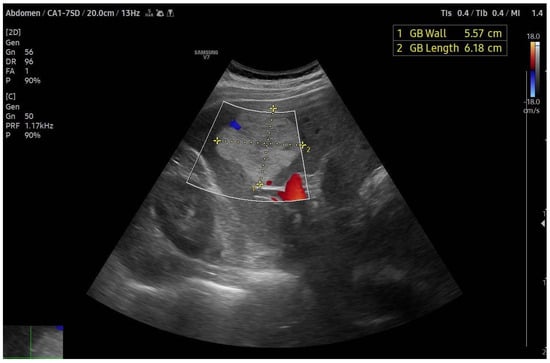

4.1. Ultrasound (US)

4.2. Contrast-Enhanced Ultrasound (CEUS)

- Klotz, T.; Montoriol, P.F.; Da Ines, D.; Petitcolin, V.; Joubert-Zakeyh, J.; Garcier, J.M. Hepatic haemangioma: Common and uncommon imaging features. Diagn. Interv. Imaging 2013, 94, 849–859. [Google Scholar] [CrossRef] [PubMed]

- Mamone, G.; Di Piazza, A.; Carollo, V.; Cannataci, C.; Cortis, K.; Bartolotta, T.V.; Miraglia, R. Imaging of hepatic hemangioma: From A to Z. Abdom. Radiol. 2020, 45, 672–691. [Google Scholar] [CrossRef] [PubMed]

- Caseiro-Alves, F.; Brito, J.; Araujo, A.E.; Belo-Soares, P.; Rodrigues, H.; Cipriano, A.; Sousa, D.; Mathieu, D. Liver haemangioma: Common and uncommon findings and how to improve the differential diagnosis. Eur. Radiol. 2007, 17, 1544–1554. [Google Scholar] [CrossRef] [PubMed]